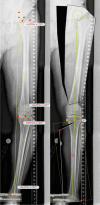

Material and methods: In this retrospective study, 40 DLOs were followed up in 34 patients. In group one (13 cases, age 45.6 (16-61) years) a varization DLO was performed, in group two (24 cases, age 48.3 (20-61) years) a valgization DLO was performed. The pre- and postoperative clinical scores were recorded: Tegner Activity score, Japanese knee society Score and Lysholm Score. The leg axis and knee joint angles were recorded and compared pre- and postoperatively.

Results: The follow-up period was 24 (6-81) months. The follow-up rate was 73% (27/37). The preoperative leg axis in group one showed an average valgus of 15.9° (9-40°). Group two had an average varus of 12° (8-21°). Postoperatively, the leg axis was 3.4° varus in group one and 0.5° valgus in group two. The mLDFA changed in group one from 83.2° to 90.9°, the MPTA from 95.5° to 87.0°. In group two, the mLDFA changed from 91.9° to 85.9° and the MPTA from 83.3° to 88.3° on average. The JLCA changed in group one from - 3.2 (- 5°-0°) to - 0.5° (- 3-2°) postoperative and in group two from 3.3° (1-8°) to 3.0° (0-6°) postoperative. Tegner score, Lysholm score and Japanese knee Society score all improved significantly in both groups. Patients with a valgus axis have worse clinical scores before surgery than the varus group, but the varus group shows a higher potential for improvement postoperatively. Every patient stated that they would have the operation performed again. Complications were rare, two overcorrections required corrective surgery. Two hinge fractures were treated intraoperatively with additional contralateral plate osteosynthesis.